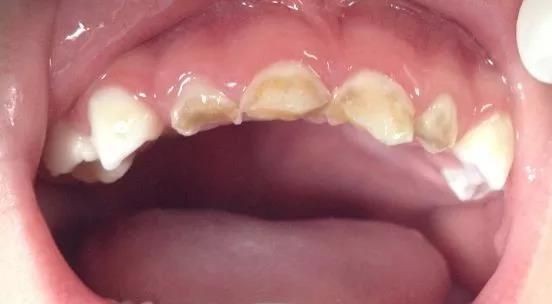

还有一种情况“奶瓶龋”,它里头长这样子↓↓

奶瓶龋常见于幼儿的牙齿(图为奶瓶龋)